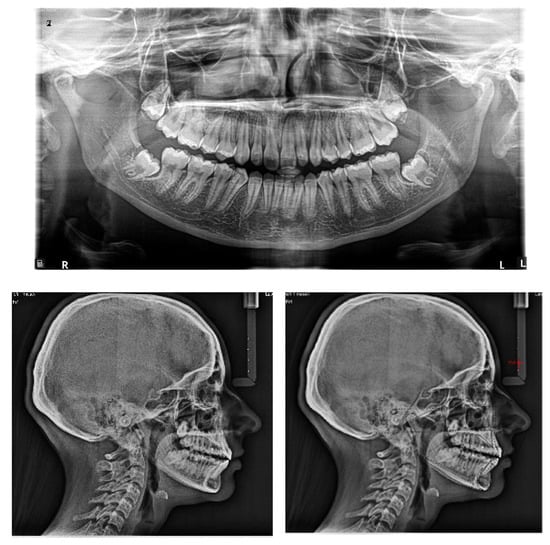

At the end of the treatment, cephalometric radiographs show the good control of the upper and lower inclination. The radiographic evaluation shows an ideal root parallelism and a preserved periodontal health in the canine region (Figure 18). Retention was achieved through Vivera in the upper arch and via a bonded lingual retainer in the lower arch. No TAD failures were observed.

Figure 18.

Final radiographs and landmarks.